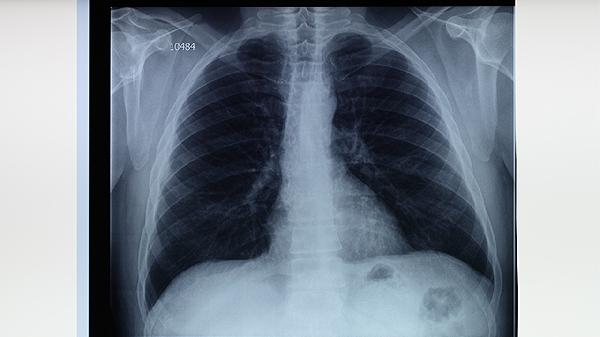

胸部X线可显示肺结核特征性病变,如上肺野浸润影、空洞形成或纤维钙化灶。典型影像表现为多形态病灶共存,但需与肺炎、肺癌等疾病鉴别。CT检查能更清晰显示微小病灶和纵隔淋巴结肿大。影像学异常需结合病原学检查确诊,单纯影像表现不能作为最终诊断依据。